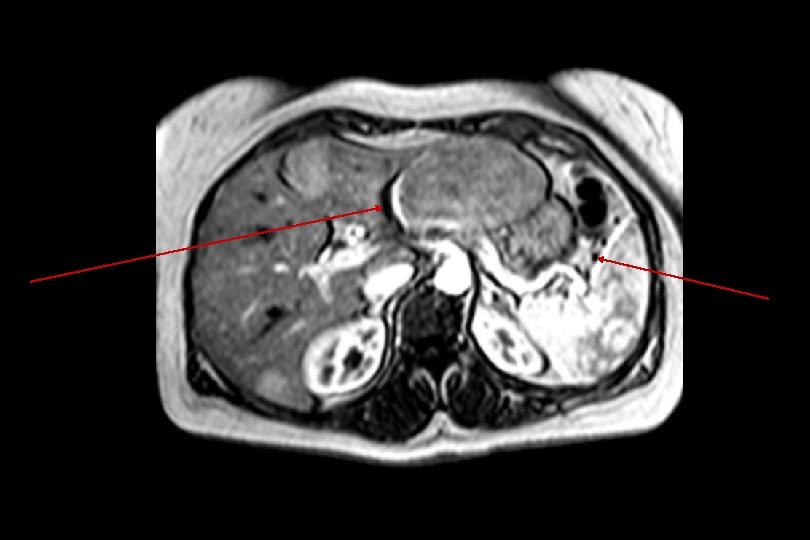

TE = 2, 3 ms Opposition de phase TE = 4, 6 ms Phase Stéatose (= dépôt de graisse dans le foie) homogène

STEATOSE HEPATIQUE • En phase : signal iso intense • En opposition de phase : signal hypo intense

CANCER COLIQUE Ilot de foie stéatosique